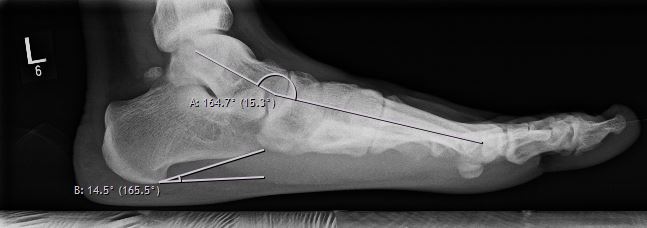

Bei einem Knick-Senkfuß-Spreizfuß kommt es zu einer Abflachung des Längsgewölbes im Sinne eines Platt- oder Senkfußes. Zusätzlich kippt die Ferse / der Rückfuß nach innen (ähnlich eines X-Beines am Knie). Hierdurch entsteht eine einseitige Belastung des Fußes/Sprunggelenkes, welches zu Beschwerden anfangs im Innenbandbereich und im Verlauf auch im Bereich des Außenbandbereiches führen kann.